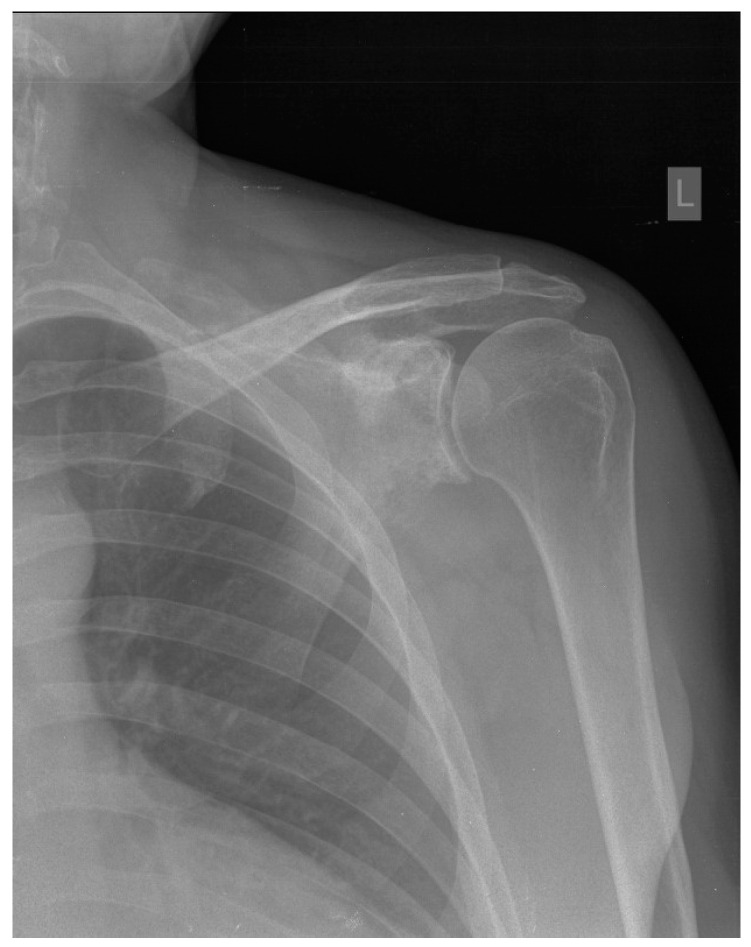

Primary bone lymphoma of the scapula is a rare tumor that usually causes local pain. The presented patient suffered for two years from paresthesia, tingling, numbness, and edema of the little and ring fingers. The 45-year-old man underwent several radiological and neurological assessments of the palm, elbow, and neck before radiographs revealed a tumor of the left shoulder. Once diffuse large B-cell lymphoma was confirmed, immunochemotherapy with rituximab, cyclophosphamide, doxorubicin, vincristine, and methylprednisolone (R-CHOP) started. The treatment was accompanied by antiviral treatment with lamivudine due to positive hepatitis B virus serology, specifically anti-HBs (hepatitis B surface) antibody, total anti-HBc (hepatitis B core) antibody, and anti-HBe (hepatitis B e antigen) antibody, together with bisphosphonate treatment for the prevention of bone resorption. Once immunochemotherapy was finished, the treatment was supplemented by radiotherapy of the shoulder. After more than three years of remission, the patient had an ischemic stroke manifesting with right-sided hemiparesis. Following physical therapy, the patient is currently in the process of evaluation for thrombophilia, as well as further cardiac assessment due to the positive transcranial Doppler bubble test, setting high suspicion for the presence of patent foramen ovale.